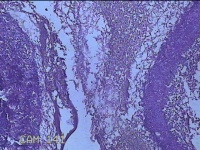

右侧窦腔内容物

性别

男

年龄

49岁

临床诊断

1.慢性鼻窦炎 2.鼻中隔偏曲 3.变应性鼻炎

一般病史

鼻塞、脓涕2月,加重伴涕中带血1周。

标本名称

大体所见

灰白暗红色不规则碎组织1.5x1.3x0.3cm一堆。